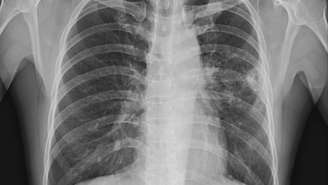

raio-x de cancer – depositphotos.com / Richmanphoto